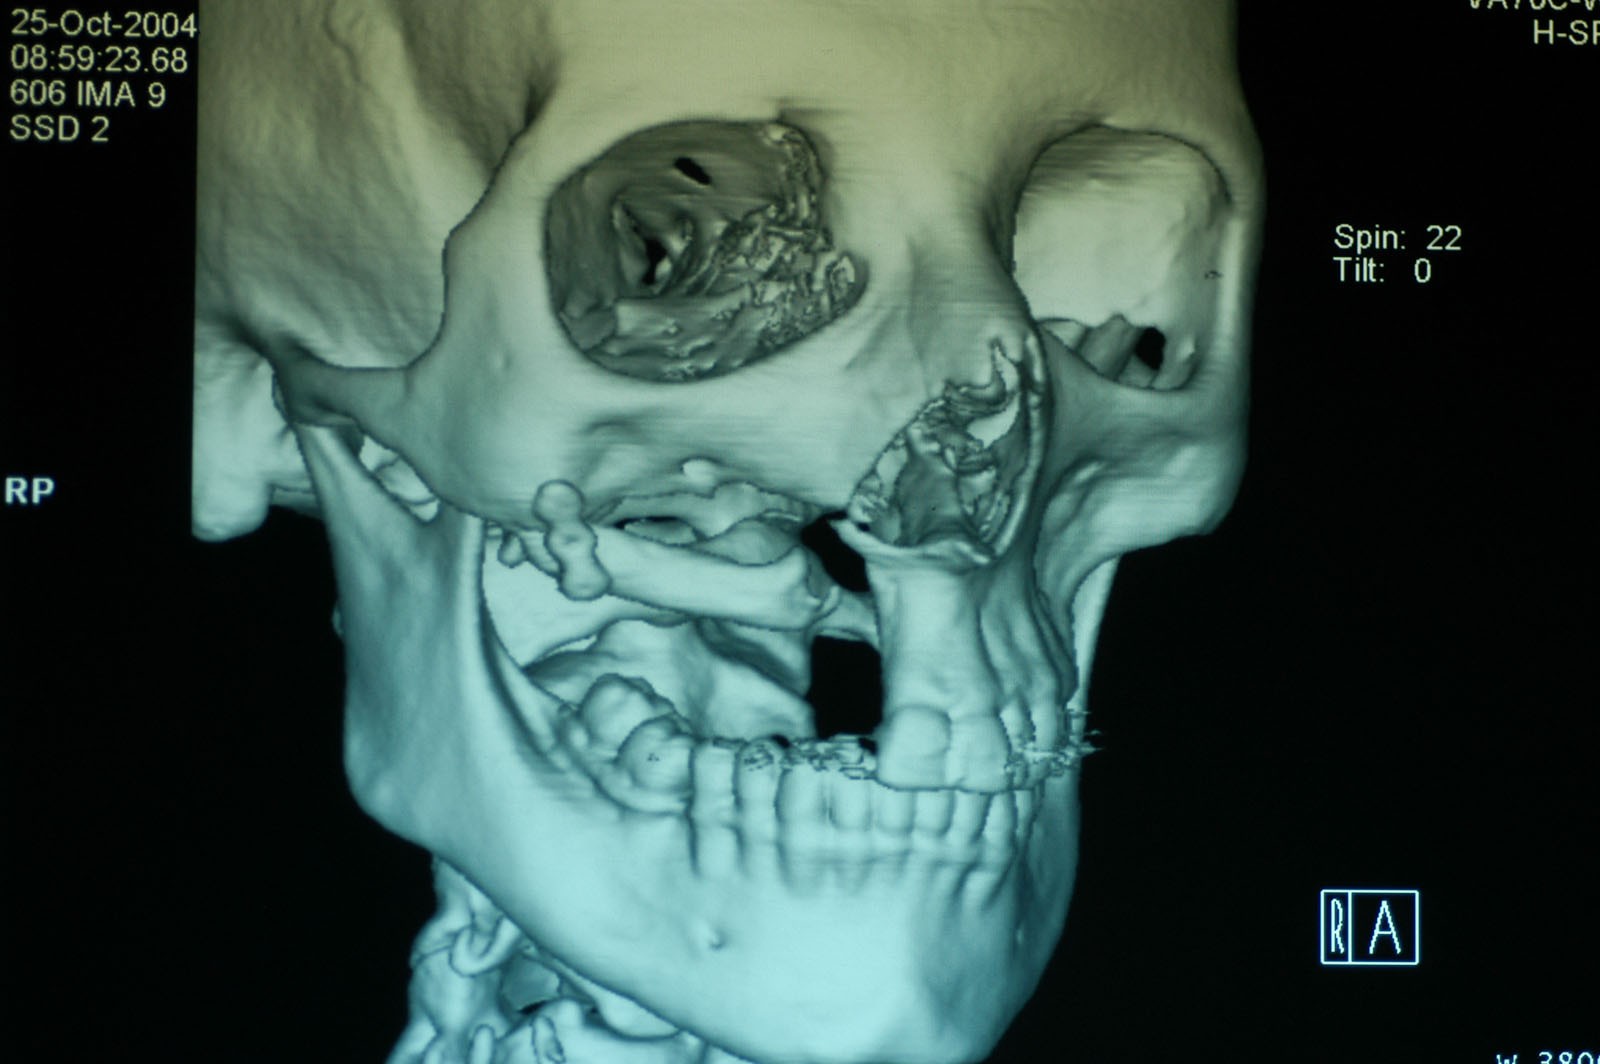

Chory po resekcji tkanek/narządów twarzoczaszki wymaga wnikliwej diagnostyki obrazującej zakres ubytku oraz stan podłoża kostnego. Wykonuje się zdjęcia radiologiczne RTG pantomograficzne szczęk OPG, konwencjonalną tomografię komputerową CT, stożkową tomografię komputerową CBCT, ukazującą trójwymiarowy obraz twarzoczaszki, oraz w razie potrzeby rezonans magnetyczny NMR. Możliwy jest również druk modeli 3D w skali 1:1 dowolnej części twarzoczaszki.

Diagnostyka ma za zadanie wykluczenie wznowy wyciętego nowotworu oraz pomoc w ocenie tkanki kostnej w okolicy ubytku. Ocena kości pozwala na zaplanowanie zabiegu wszczepienia implantów jako przyszłego fundamentu niezbędnego dla mocowania protez poresekcyjnych lub epitez twarzy.

Zastosowanie współczesnych technik obrazowania trójwymiarowego umożliwia precyzyjne zaplanowanie pozycji implantów czaszkowych, tak by ektoprotezę stabilnie osadzić na podłożu.